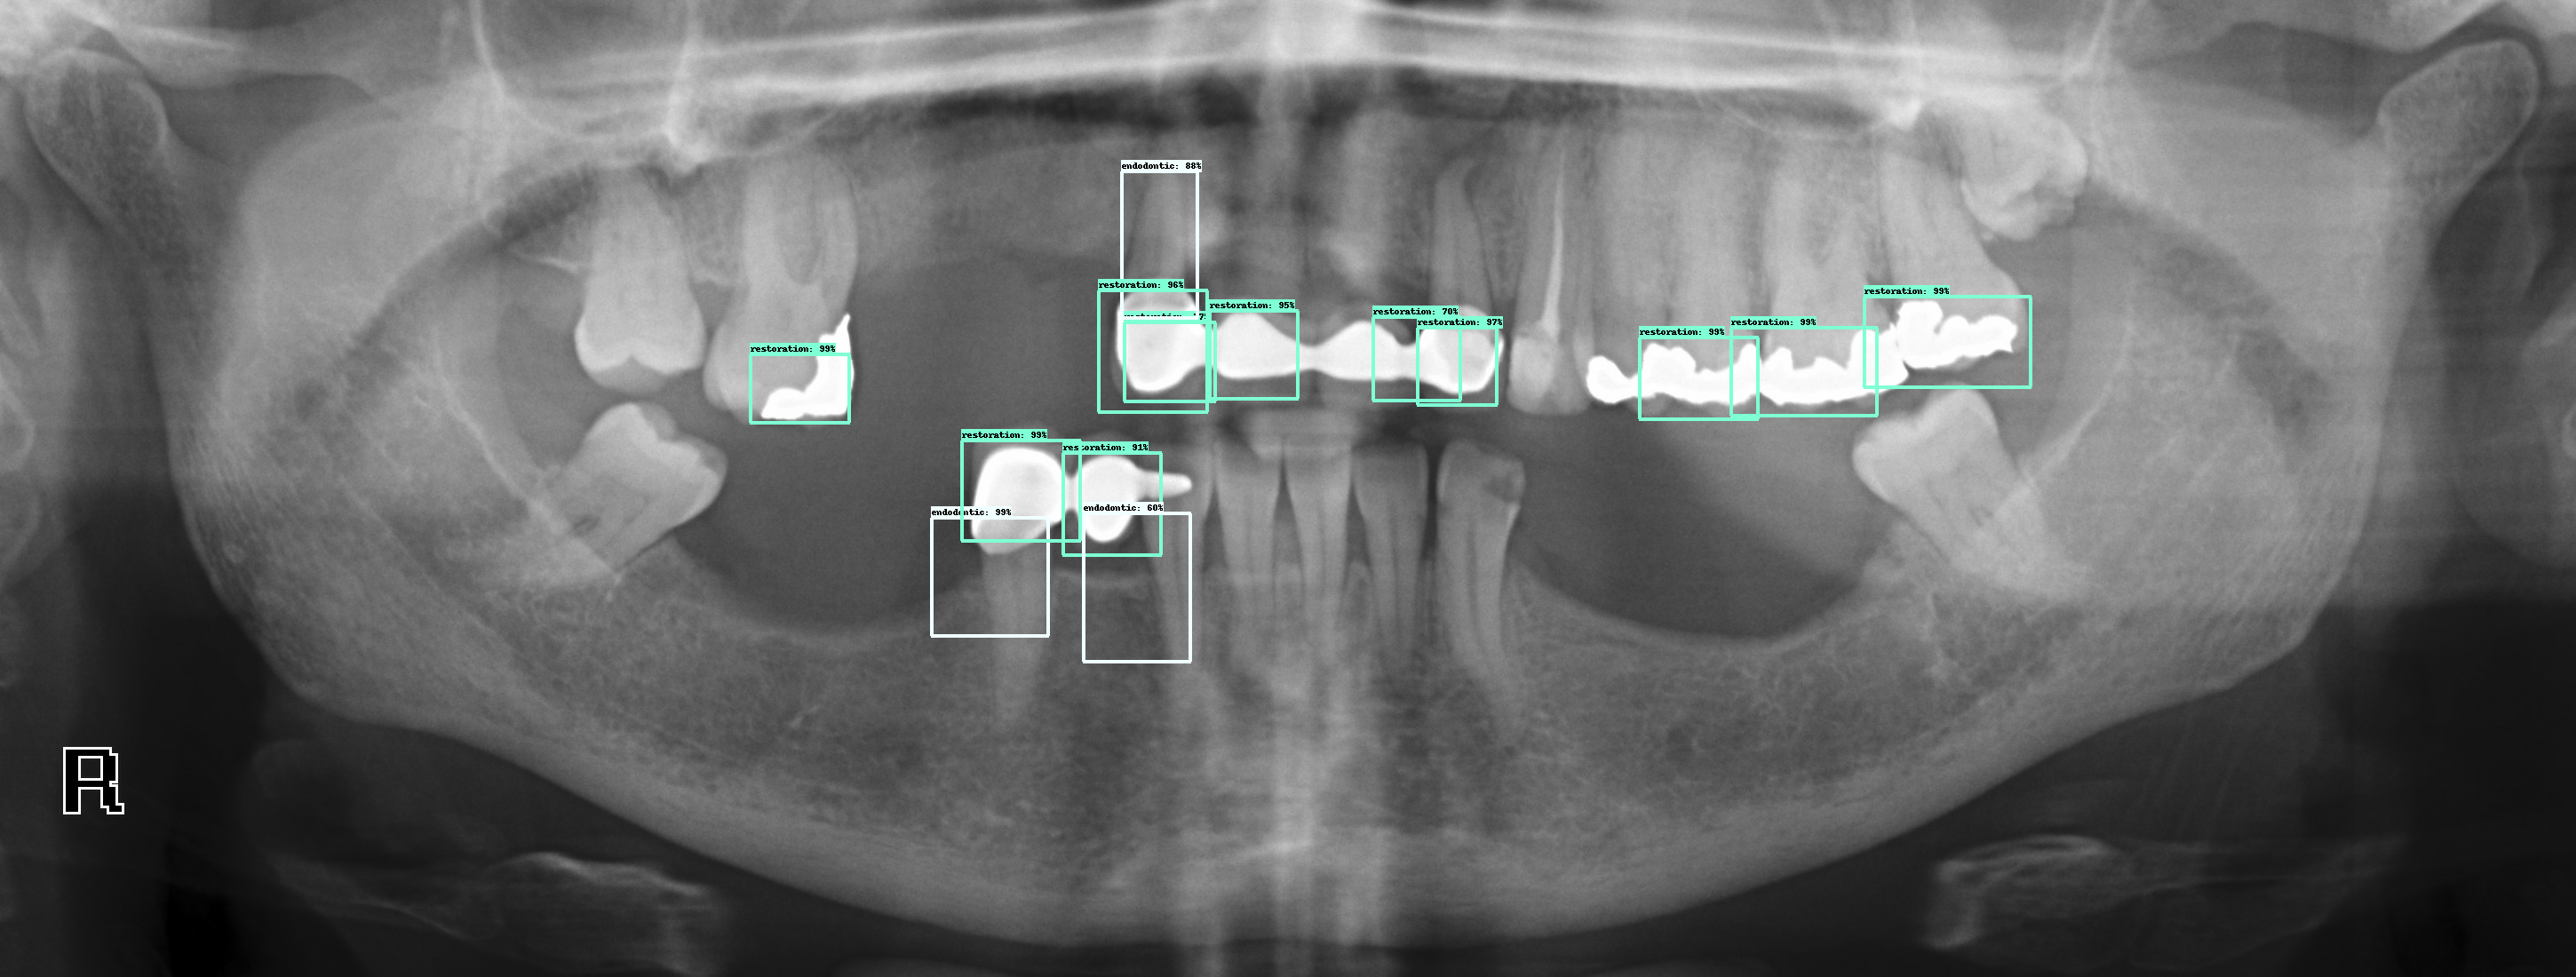

What type of X rays are needed for implant placement?

Cone ray CT is a type of radiography that produces 3D images of dental structures, soft tissues, nerves, and bones. It helps locate dental implants and assesses cysts and tumors in the mouth and face. He may also see problems with gums, tooth roots and jaws.

What type of radiograph is best for placing dental implants and why?

Periapical radiography is used to find the presence of pathos and the location of anatomical structures around the implant site and to assess the implant after surgery.